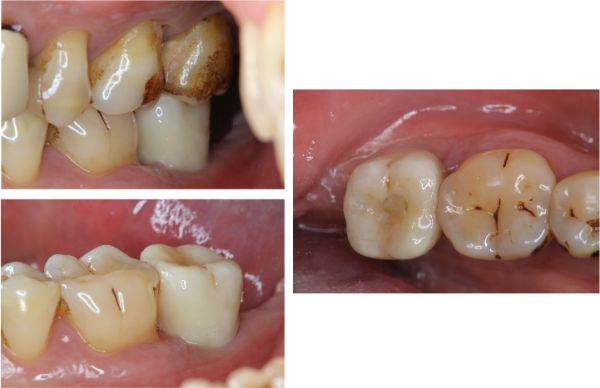

治療前,左下第二大臼齒牙周病

牙周破壞,牙齒動搖

照相比色